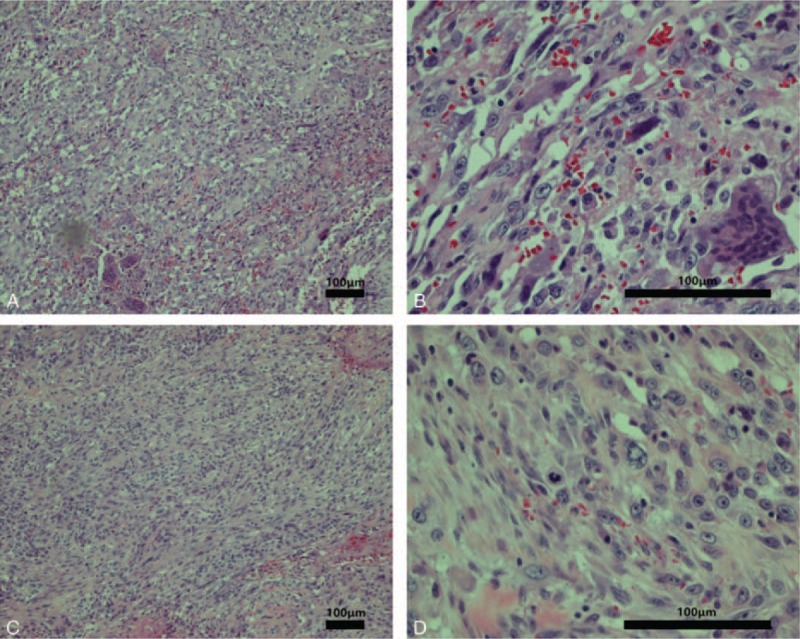

Microscopically, the tumor was a poorly differentiated carcinoma containing a component of sarcoma-like (spindle and/or giant cell) differentiation (Fig. 3). Adenoid structures were visible in the focal area. The tumor cells had spindle-shaped nuclei with occasional mitotic figures forming bundles and whirls. Oval and epithelioid cells were also present, and giant cells, including multinucleated cells and tumor giant cells, were visible in the focal section. There were also necrotic regions within the focal section. No heterologous sarcomatous elements were identified. No metastasis was found in the regional lymph nodes.